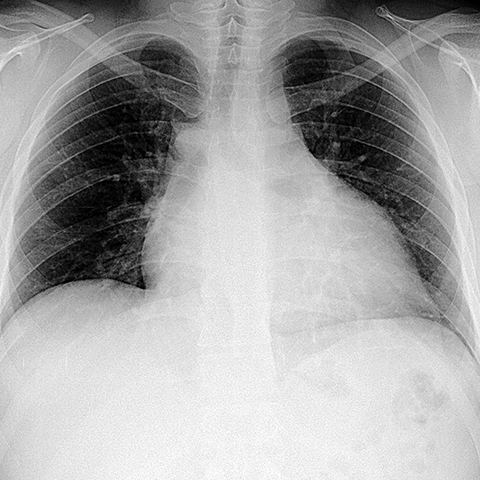

Pericardial Effusion [6 of 8]